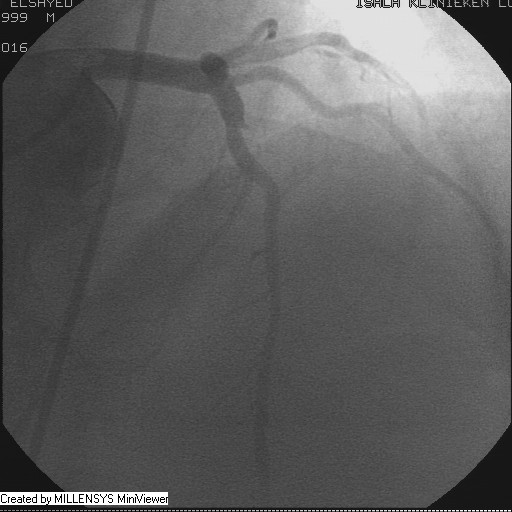

Patient transfered to Cardiac Catheterization Laboratory, coronary angiography showed atherosclerotic coronaries but without significant lesions, especially LAD that was patent with TIMI 3 flow (Figure 1- 5). Re-evaluation of the Angiography showed a small stump that can be for an occluded 1st diagonal (Figure 2a), at that level the LAD has a non-significant lesion.

After crossing with the PTCA wire, a minimal flow started to appear in the diagonal branch (Figure 6), then LAD was wired, then a 2x15mm Balloon was used to pre-dilate (Figure 7,8), a big diagonal branch appeared with proximal thrombotic tight lesion (Figure 9), the diagonal angle to LAD was about 90 degree (Figure 10), so provisional stenting done to diagonal from its ostium with 3x20mm PROMUS ELEMENT PLUS DES (Figure 11,12), with good final result (Figures 13&14).

Figure 5